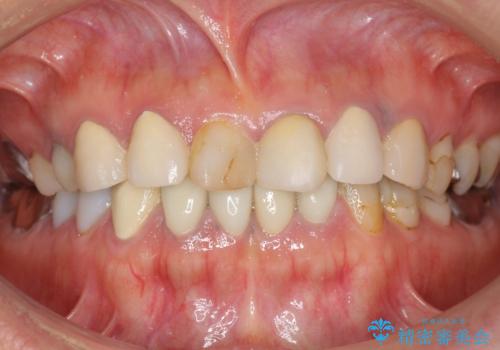

被せ物を入れたばかりの歯が痛む 40代女性

- 他院で被せ物を入れたばかりの歯が痛むことを主訴に来院された患者様です。

「様子を見ましょう」と言われ何もしてもらえず、痛みが続き不安になってしまったとのことでした。

精査したところ、被せ物を入れたばかりの右下の小臼歯(右下5)は不可逆性歯髄炎により神経をとる処置(抜髄)が必要な状態でした。

根管治療後、セラミッククラウンによる補綴治療を行いました。

根管治療により痛みがなくなり、ご安心頂けました。

セラミッククラウンの自然な仕上がりにも喜んで下さいました。

クラウンの種類:オールセラミッククラウン エコノミー